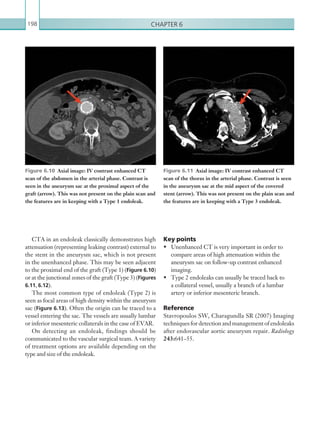

patient.

Whenever the scan is negative it is important to look

foranothercauseforchestpainorshortnessofbreathto

explainthepatient’ssymptoms.Theaortaandtheheart

should be assessed for aortic pathology or myocardial

infarction. A septal infarct on a CTPA scan is shown